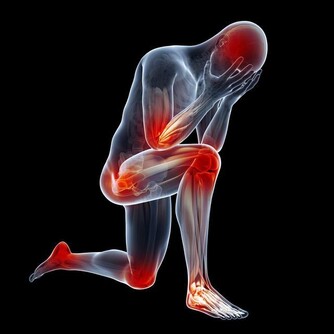

很多人都存在一個認識誤區,以為身體爆青筋是正常的。其實那並不是青筋而是血管,也就是說無論出現在身體的哪個部位都是一種報警信號。下面就給大家詳細介紹相關知識。.